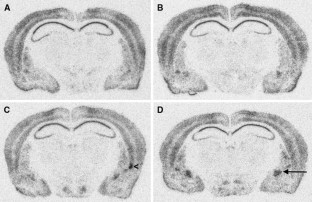

In search for the substrate of naltrexone and acamprosate action on alcohol craving, we investigated the effects of ethanol alone and combined with naltrexone or acamprosate on expression of nerve growth factor-inducible clone A (NGFI-A; zif268). In Experiments 1 and 3, alcohol (2 g/kg) alone or in combination with naltrexone (15 mg/kg) or acamprosate (300 mg/kg) was injected intraperitoneally into mice. In Experiment 2, treatment was nor-BNI (0.5 mg/kg) to investigate whether the effect of naltrexone involved blockade of κ-opioid receptors. Both ethanol and naltrexone alone induced NGFI-A in the central amygdala, but not in several other areas; these effects were additive. However, acamprosate alone or in combination with ethanol had no effect on NGFI-A mRNA, while nor-BNI induced NGFI-A mRNA in the basolateral amygdala. The central amygdala appears to be an important target of both alcohol and naltrexone. Acamprosate may not share the site of action with naltrexone despite being used for the same therapeutic purpose.

Fig. 1

Fig. 2